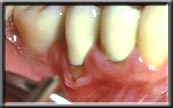

The replacement of missing attached gum is called gingival grafting. The muscle that is pulling down on the edge of the gum is first surgically resected and repositioned away from the gum margin. Then a small piece of attached gingiva is taken from the roof of the mouth, just adjacent to the back teeth, and transplanted to the site in question. The new tissue reattaches and reforms a new layer of attached gum, which should last a lifetime with proper care. The roof of the mouth heals quickly, just like a skinned knee might. With this procedure the root is not covered, and the tissue stays at the same level as before, except with attached gingiva at the margin. These procedures are very easy on the patient, and rarely require more than over-the-counter pain pills post-operatively (ibuprofen). Routine gum grafts ("gingival grafts") do not cover up the exposed root surface - if this is desired, a different technique is used (See Cosmetic Procedures, Root Coverage). Covering the root does not make the tooth stronger, for the bone, which actually holds the tooth in place, does not change regardless of the new gum level. Rather, root coverage procedures are primarily done for cosmetic reasons, or when there is exceptional root sensitivity after recession.